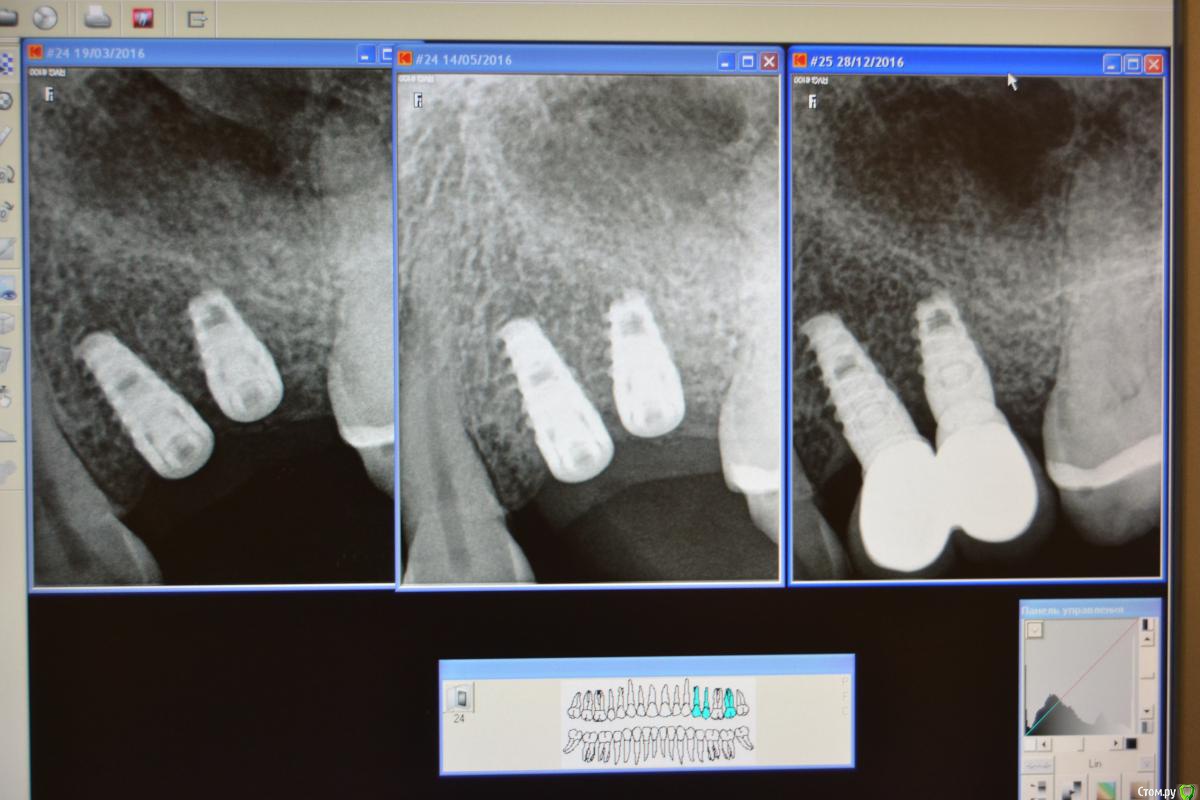

dantist_movani Опубликовано 5 февраля, 2017 Поделиться Опубликовано 5 февраля, 2017 (изменено) Имплантаты niko leader. 3.6*10 мм и 3.6*8 мм в позиции 2.4 и 2.5.Тот случай когда пациент уверен в тебе больше, чем ты сам. Руки тряслись, делал без хирургического шаблона. Первый имплантат, в области 2.4 не заглубил, стабильности имплантата в области 2.5 не было, прокручивался. После операции сделали снимок сразу расстроился, то что криво закрутил, расстояние между имплантатами 1.3 мм в области заглушек. Через 10 дней сняли швы, все хорошо...Через месяца два в области 2.5 над заглушкой свищ с отделяемым. Сделал анестезию, кюретаж над заглушкой, назначил антибактериальную и противовоспалительную, все нормализовалось. Через 5 месяцев ФДМ, все стабильно и через 3 недели коронки у ортопеда. Жуём уже 8 месяцев, Слава Богу!!! Изменено 5 февраля, 2017 пользователем dantist_movani Ссылка на комментарий